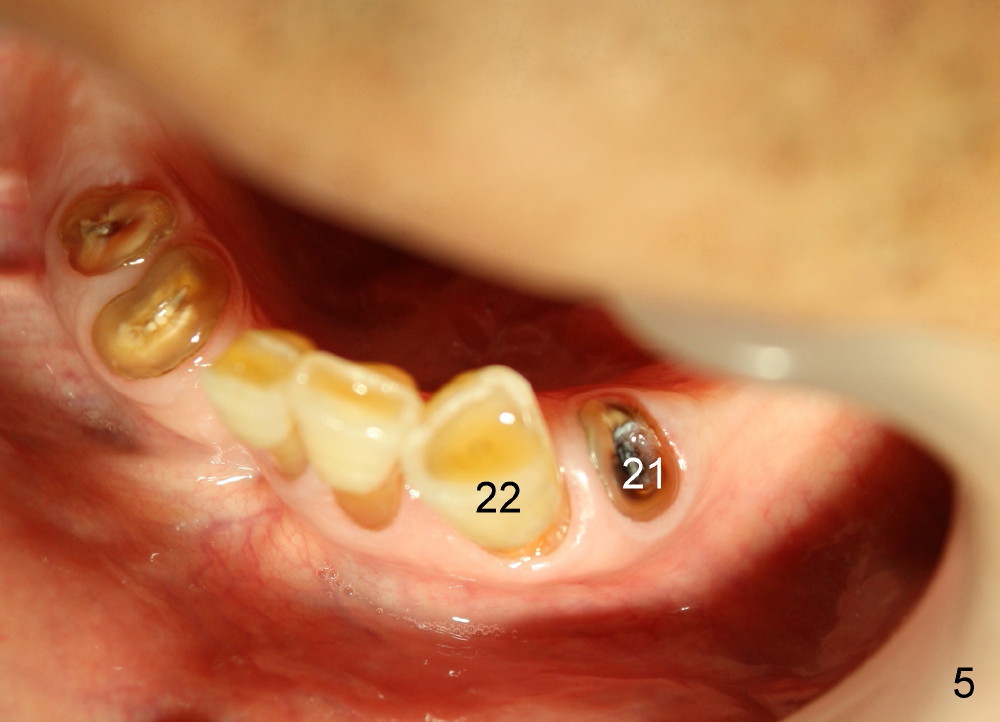

The lower left quadrant needs 3 implants (Fig.1,5: #19-21). The neighboring tooth #22 has periapical radiolucency (Fig.1 (CBCT sagittal section): *), which should be treated prior to implantation.